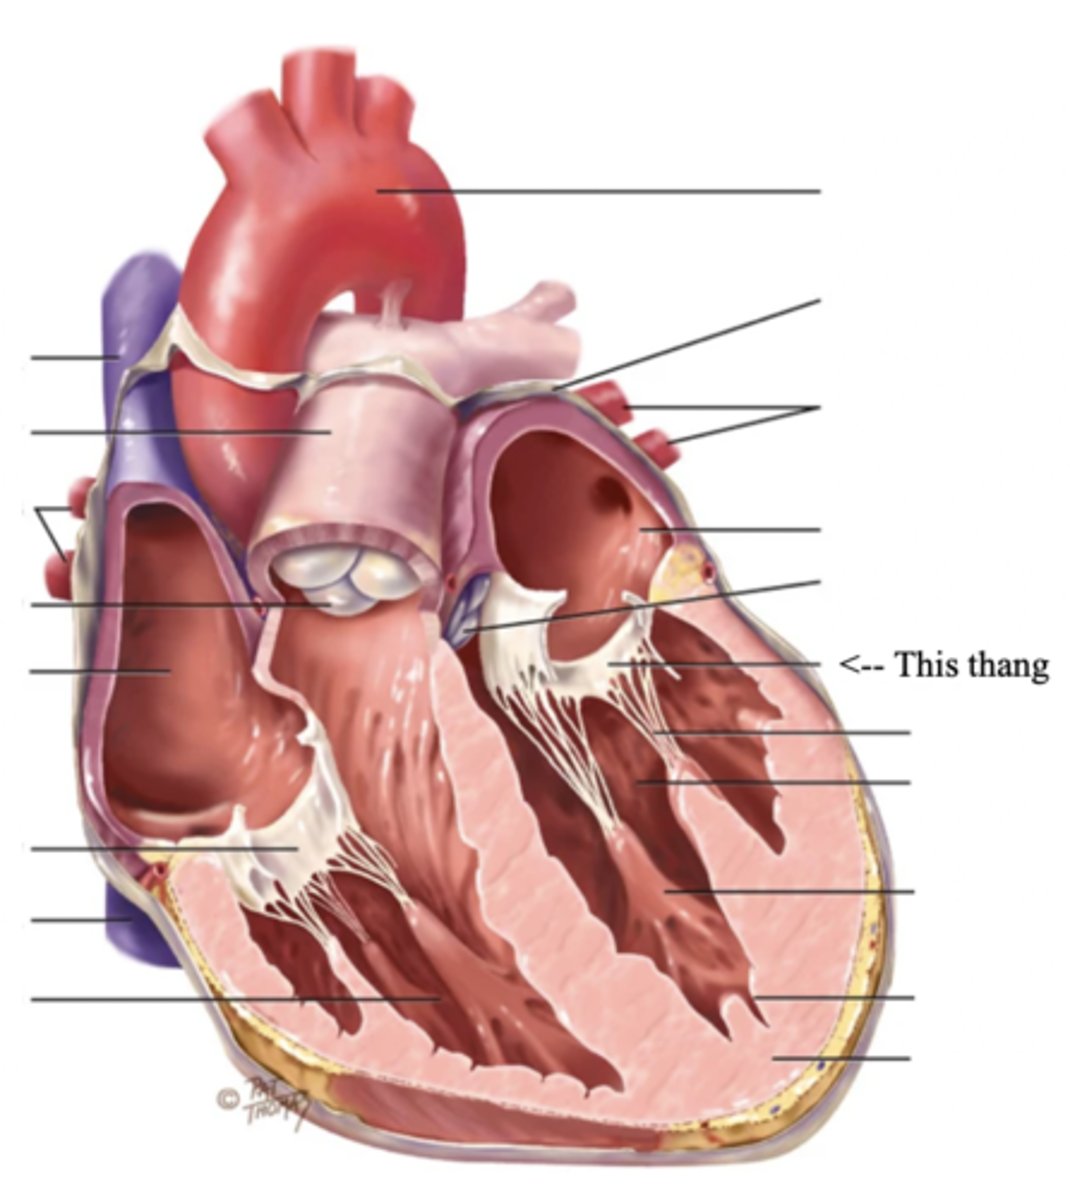

Anatomy of the Heart

Myocardium

The muscular wall of the heart; does the pumping

Endocardium

The thin layer of endothelial tissue that lines the inner surface of the heart chambers and valves

2 Types of Chambers in the Heart

- Atrium

- Ventricles

Atrium (2)

A thin-walled reservoir for holding blood, located at the upper chamber of the heart

Ventricle (2)

The thick walled muscular pumping chamber of the heart located at the bottom chamber of the heart

2 Main Types of Valves of the Heart

- Atrioventicular

- Semilunar

Atrioventricular Valves (AV) (2)

The valves that separate the atria and the ventricles

The 2 Atrioventicular Valves of the Heart

- Tricuspid

- Mitral

Tricuspid Valve

- The right AV valve separating the right atrium from the right ventricle

- Connected by 3 chordae tendinae

Mitral (Bicuspid) Valve

- The left AV valve separating the left atrium from the left ventricle

- Connected by 2 chordae tendinae

Chordae Tendinae

Fibers (heart strings) attatched to the tricuspid and mitral valve which pull it closed when papillary muscles contract, preventing back flow of blood

Semilunar Valves (SV) (2)

Valves located between the ventricles and the pulmonary arteries and aorta

The 2 Semilunar Valves of the Heart

- Pulmonic

- Aortic

Pulmonic Valve

The SV valve of the right side of the heart

Aortic Valve

The SV valve of the left side of the heart